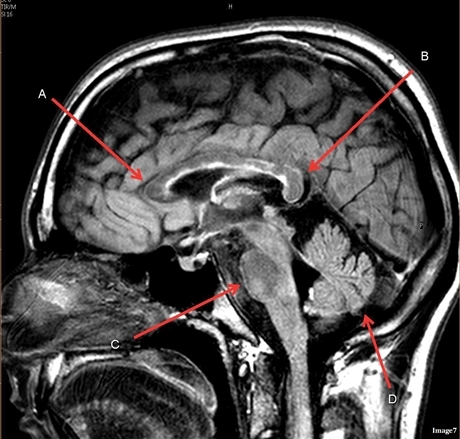

Image weighting and axis

T1 Sagittal

A

Lateral Ventricle

B

Corpus Callosum

C

Thalamus

D

Tentorium